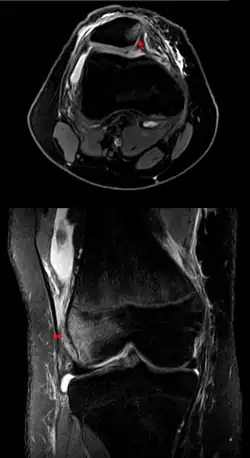

![]() | |

| Patellar luxation on radiograph: Left before, right after reduction; after reduction, the patella is still displaced. | |